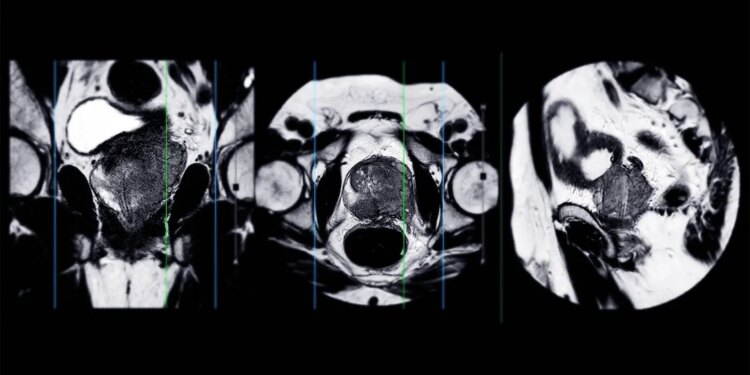

- A pretreatment MRI in men undergoing radical prostatectomy can provide independent prognostic value for oncologic outcomes, a systematic review and meta-analysis indicated.

- MRI-detected extraprostatic extension and seminal vesicle invasion were independently associated with outcomes including biochemical recurrence and metastatic failure.

- Several quantitative MRI-derived parameters were prognostic for biochemical recurrence, including Prostate Imaging Reporting and Data System scores of 4 or 5 and tumor diameter ≥20 mm.

An MRI before treatment in men undergoing radical prostatectomy can provide independent prognostic value for oncologic outcomes, according to results from a systematic review and meta-analysis.